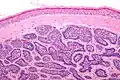

Dermal cylindromas are:

- Dermal lesions consisting of nests of cells that are surrounded by hyaline (i.e., glassy, eosinophilic, acellular) material and have:

- Hyperchromatic nuclei that may palisade (columnar nuclei arranged around the periphery of the cell nests with their short axis tangential to the nest periphery), and

- Cells with lighter staining ovoid nuclei at their centre.

They lack of a significant number of lymphocytes; this differentiates them from spiradenomas.

Micrograph of a dermal cylindroma in H&E stain. -

Micrograph of dermal cylindroma in H&E stain. -